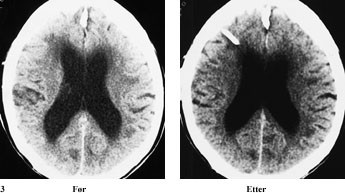

I tillegg til de kliniske symptomer baseres diagnosen normaltrykkshydrocephalus på funnene ved cerebral computertomografi (CT) (2 – 5). En CT-undersøkelse av hjernen er fortsatt en god screeningmetode, der store ventrikler, utplanert kortikalt relieff og periventrikulær lavattenuering er typisk for normaltrykkshydrocephalus (3).

Behandlingen ved normaltrykkshydrocephalus går ut på å drenere cerebrospinalvæsken via et rørsystem til bukhulen, ventrikuloperitoneal shunt (fig 1 – 3), for å normalisere og stabilisere de intrakraniale trykkforhold.